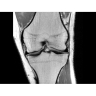

• РЧ-катушки, оптимизированные для исследования конкретных участков тела — элементы катушек высокой плотности располагаются вокруг исследуемых участков тела и при необходимости обеспечивают расширенный охват и оптимальное качество изображений при каждой процедуре.

• Широкое поле зрения — поле зрения шириной 50 см позволяет охватывать крупные анатомические области за меньшее число сканов.